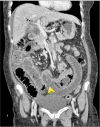

Gallstone ileus is an uncommon cause of intestinal obstruction. It may present with typical symptoms of intestinal obstruction with or without biliary sepsis. Its management strategies vary depending on the patient and operative factors. Enterotomy and stone removal alone versus synchronous cholecystectomy and fistula disconnection at the same stage, often pose a debate among surgeons. The decision for operative strategies largely depends on the surgeon's experience, patient's physiology, and operative difficulties. As literature on gall stone ileus remains insufficient at a regional level, we report four cases of gallstone ileus managed with different approaches. Three patients were managed in a staged-manner, whereas one patient received a definitive procedure performed at index surgery. Clinical challenges and associated operative strategies are discussed. Findings of the current study were compared to those of the literature. The need for a definitive fistula disconnection and repair or cholecystectomy following stone removal in these patients was subsequently discussed.